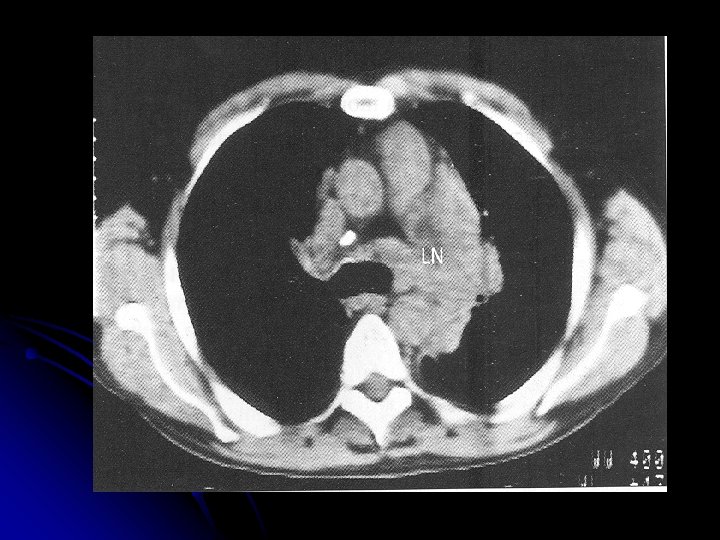

Investigations l l l l l CBP : Anemia ( normochromic / normocytic), eosinophilia, neutrophilia, lymphopenia ESR -raised LFT- (liver infil / obs at porta hepatis) RFT- prior to treatment Urate , Ca, LDH - adverse prognosis CXR- mediastinal mass CT thorax / abdomen / pelvis-for staging Other: Gallium scan, PET, Lymphangiography , Laporotomy

Staging l l Stage I : Involvement of single LN region (I) or extra lymphatic site (IAE ) Stage II : Two or more LN regions involved (II) or an extra lymphatic site and lymph node regions on the same side of diaphragm Stage III : Involvement of lymph node regions on both sides of diaphragm, with (IIIE) or without (III) localized extra lymphatic involvement or involvement of the spleen (IIS) or both (IISE) Stage IV : Involvement outside LN areas (Liver, bone marrow) A : Absence of ‘B’ symptoms B : B symptoms present